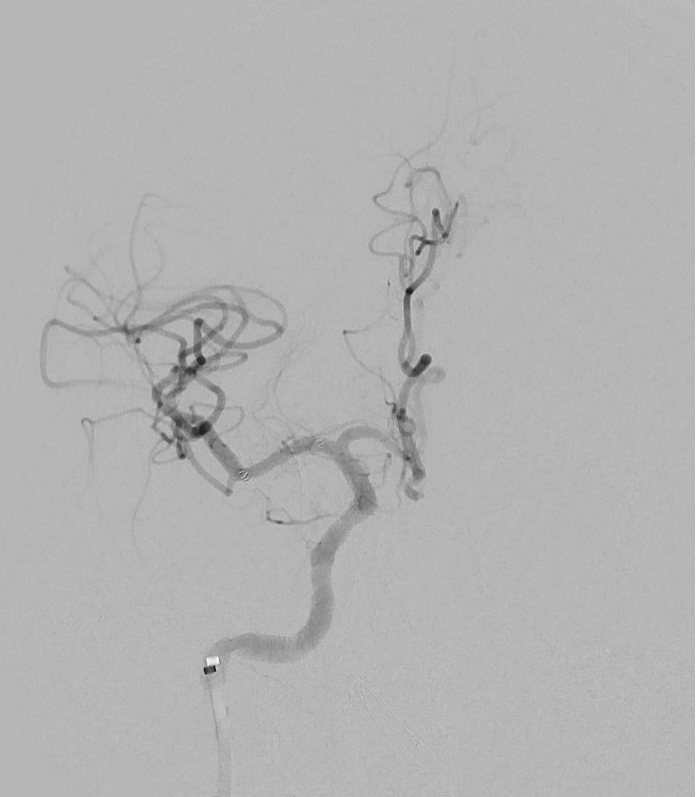

DSA:右侧大脑中动脉M1段管壁不规则溃疡斑块形成,局部重度狭窄

术后DSA:右侧大脑中动脉未见明显残余狭窄,远端分支未见残端